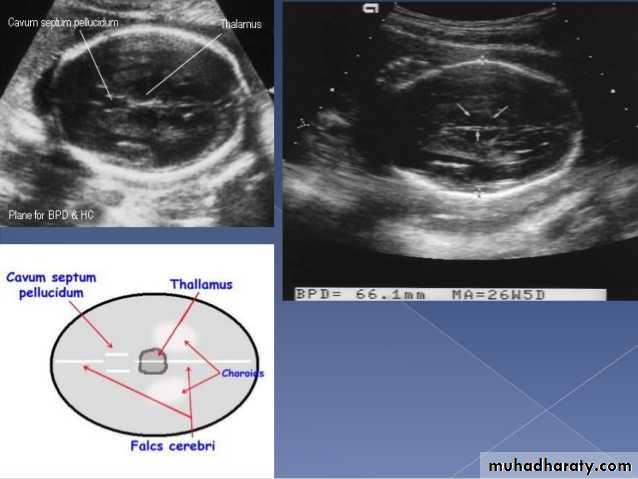

BPD together with head circumference (HC), abdominal circumference (AC), and femur length (FL) are computed to produce an estimate of fetal weight. In the second trimester this may be extrapolated to an estimate of gestational age and an estimated due date (EDD) .

The BPD should be measured on an axial plane that traverses the thalami, and cavum septum pellucidum. The transducer must be perpendicular to the central axis of the head, and thus the hemispheres and calvaria should appear symmetric.